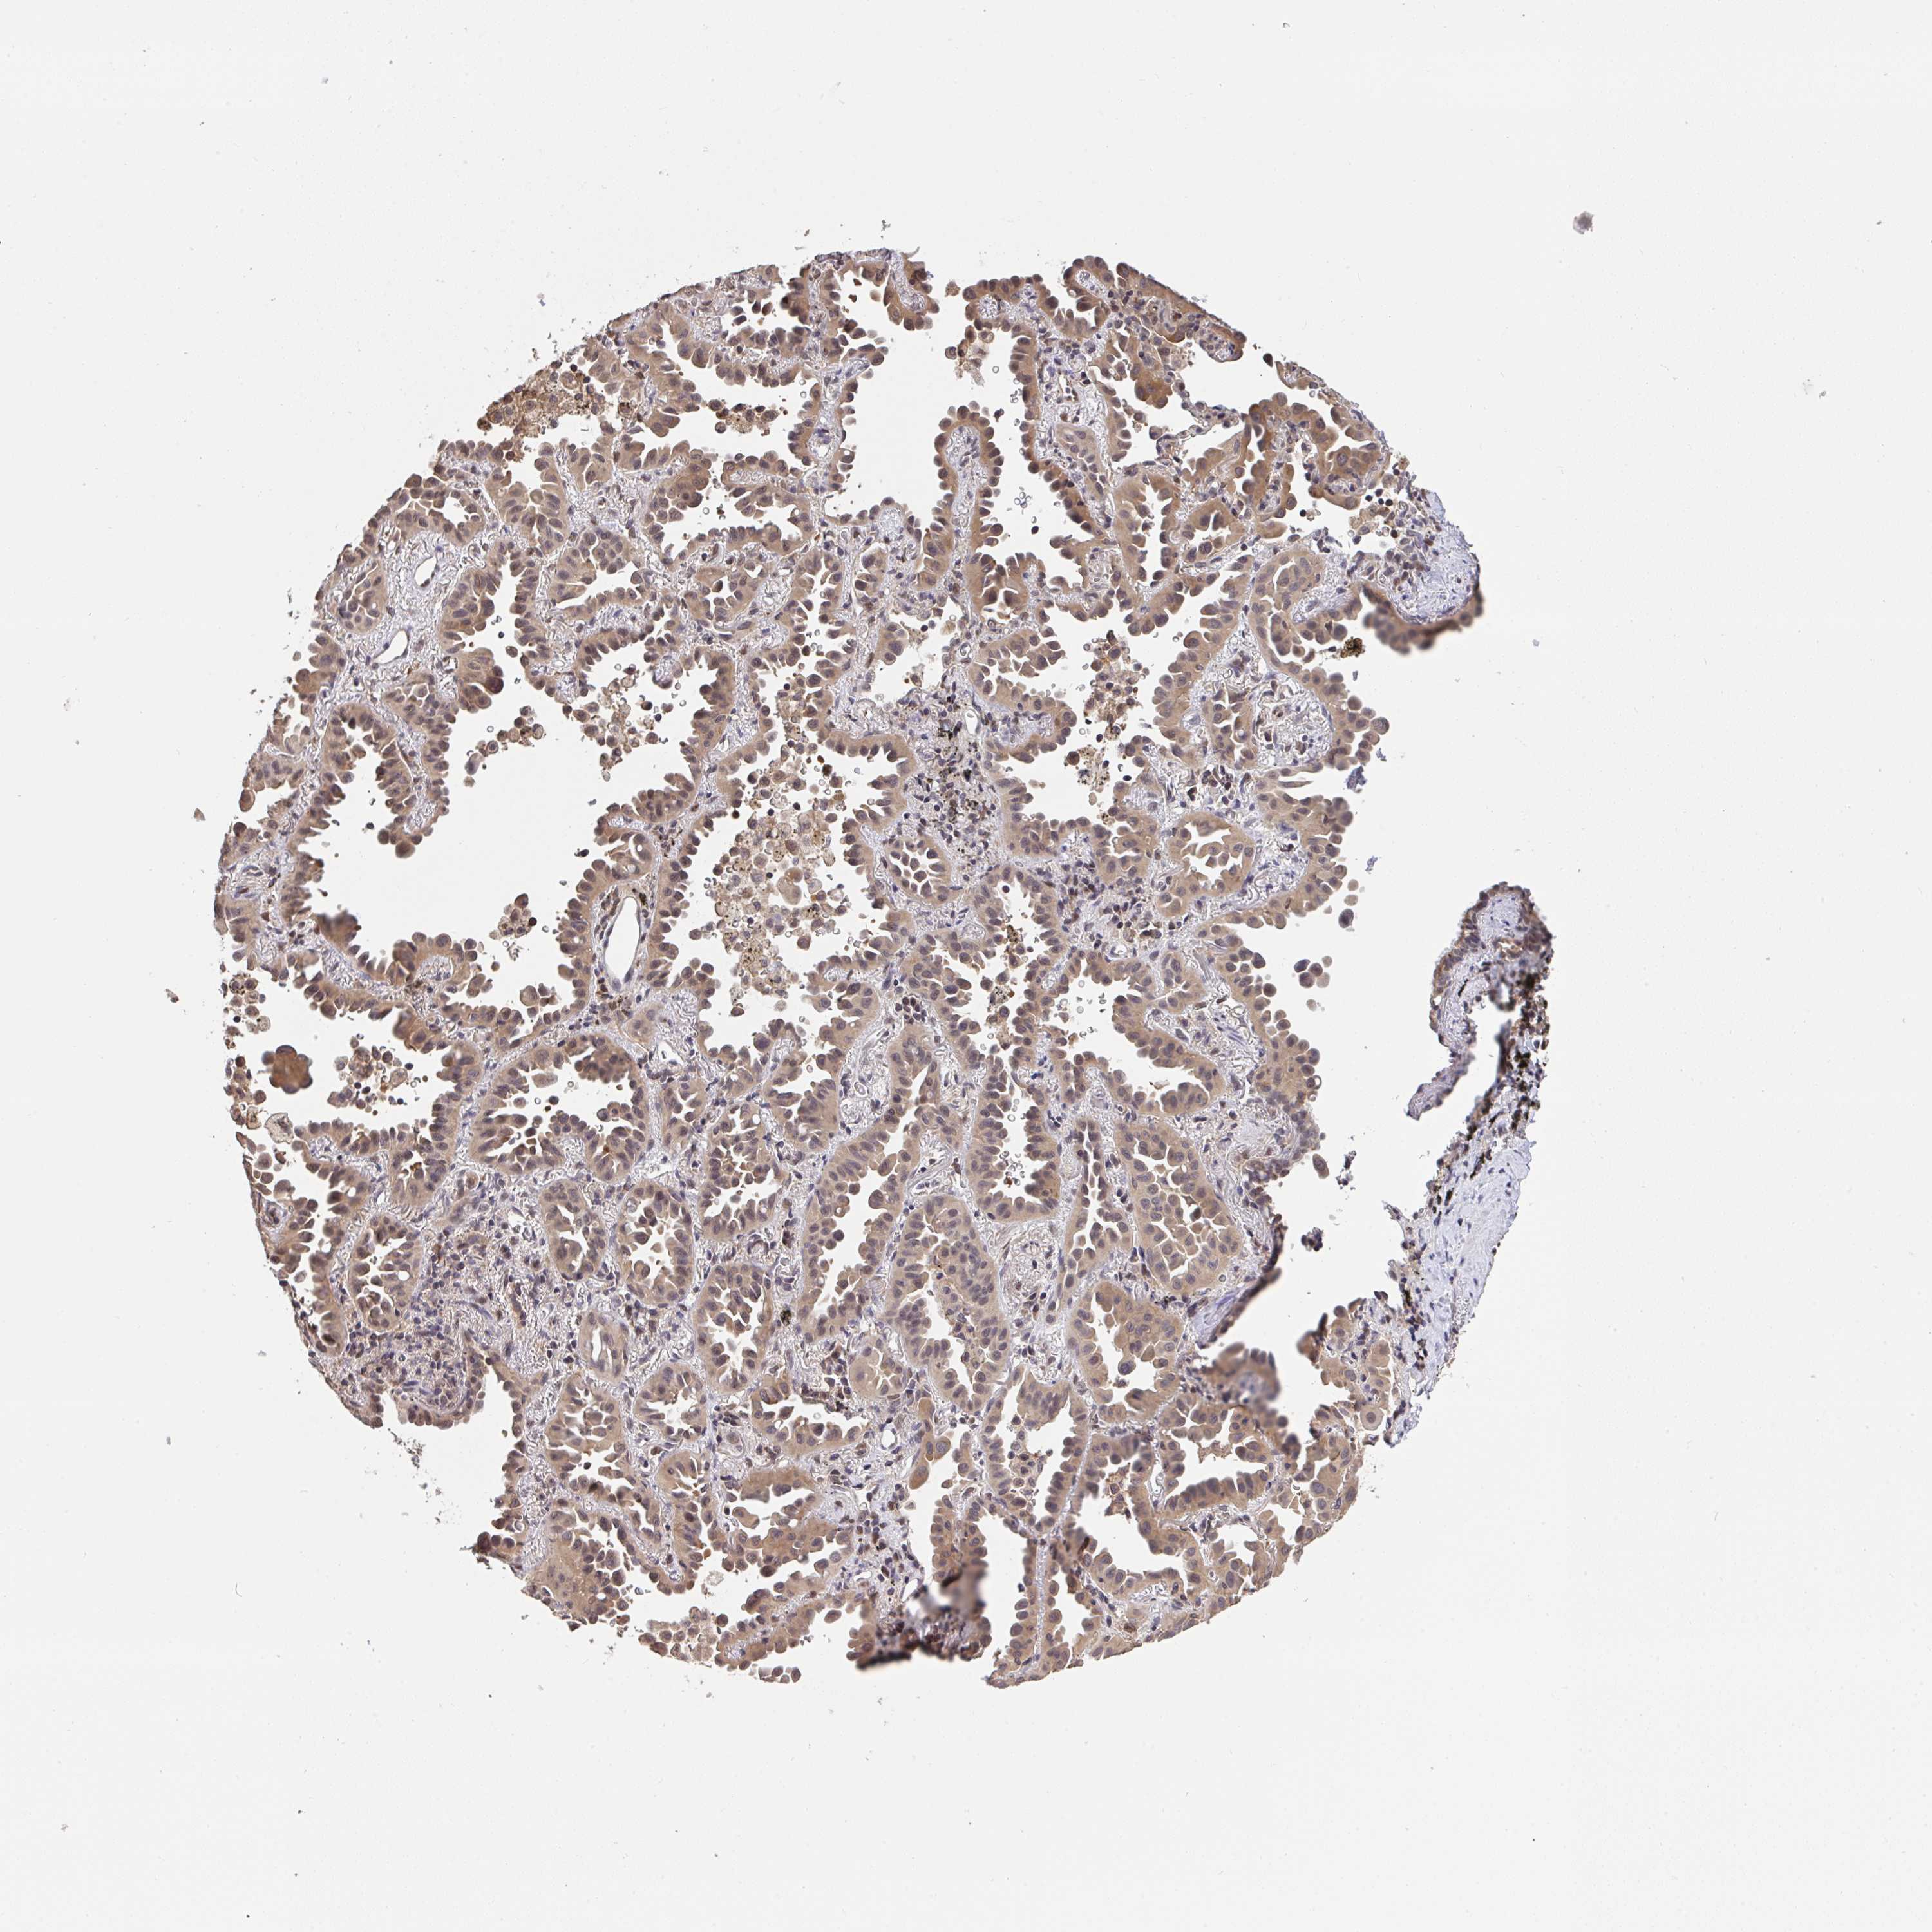

CANCER LUNG CANCER Show tissue menu

LUAD TCGA LUAD VALIDATION LUSC TCGA LUSC VALIDATION PROTEIN LUAD CPTAC PROTEIN LUSC CPTAC PROTEIN EXPRESSION